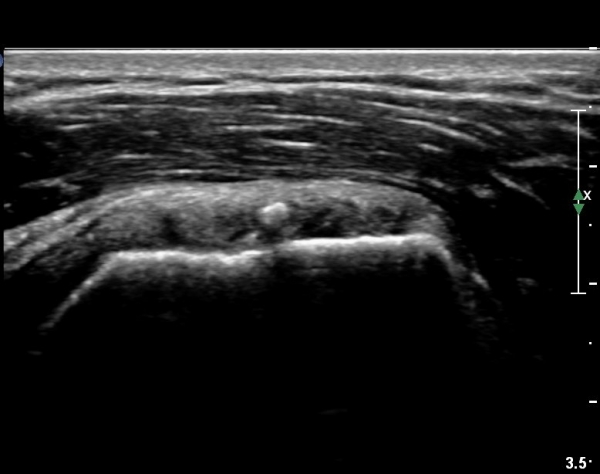

°ß°©ÇÏ±Ù°Ç ÁߺΠÁ¾´Ü¸é°Ë»ç¿¡¼­ ƯÀÌ ¼Ò°ßÀ» º¸ÀÌÁö ¾ÊÀ¸³ª(»çÁø 2) ŽÃËÀÚ¸¦ Á¶±Ý ÇϹæ(´Ù¸®ÂÊ)

À¸·Î À̵¿ÇÏ´Ï °ß°©Çϱٰdz»  ¼®È¸È­ µ¢¾î¸®°¡ °üÂûµÈ´Ù(»çÁø 3).

°ß°©ÇÏ±Ù°Ç È¾´Ü¸é°Ë»ç»ó ¼Ò°áÀý ÇÊÁú°ñº¯È­¿Í °ß°©ÇÏ±Ù°Ç Áߺο¡ °í¿¡ÄÚ µ¢¾î¸®°¡ °üÂûµÇ°í

¼®È¸ À§ÂÊ(¸Ó¸®ÂÊ)ÀÇ ÈûÁÙÀÇ Àú¿¡ÄÚ º¯È­°¡ °üÂûµÈ´Ù(»çÁø 4, 5).